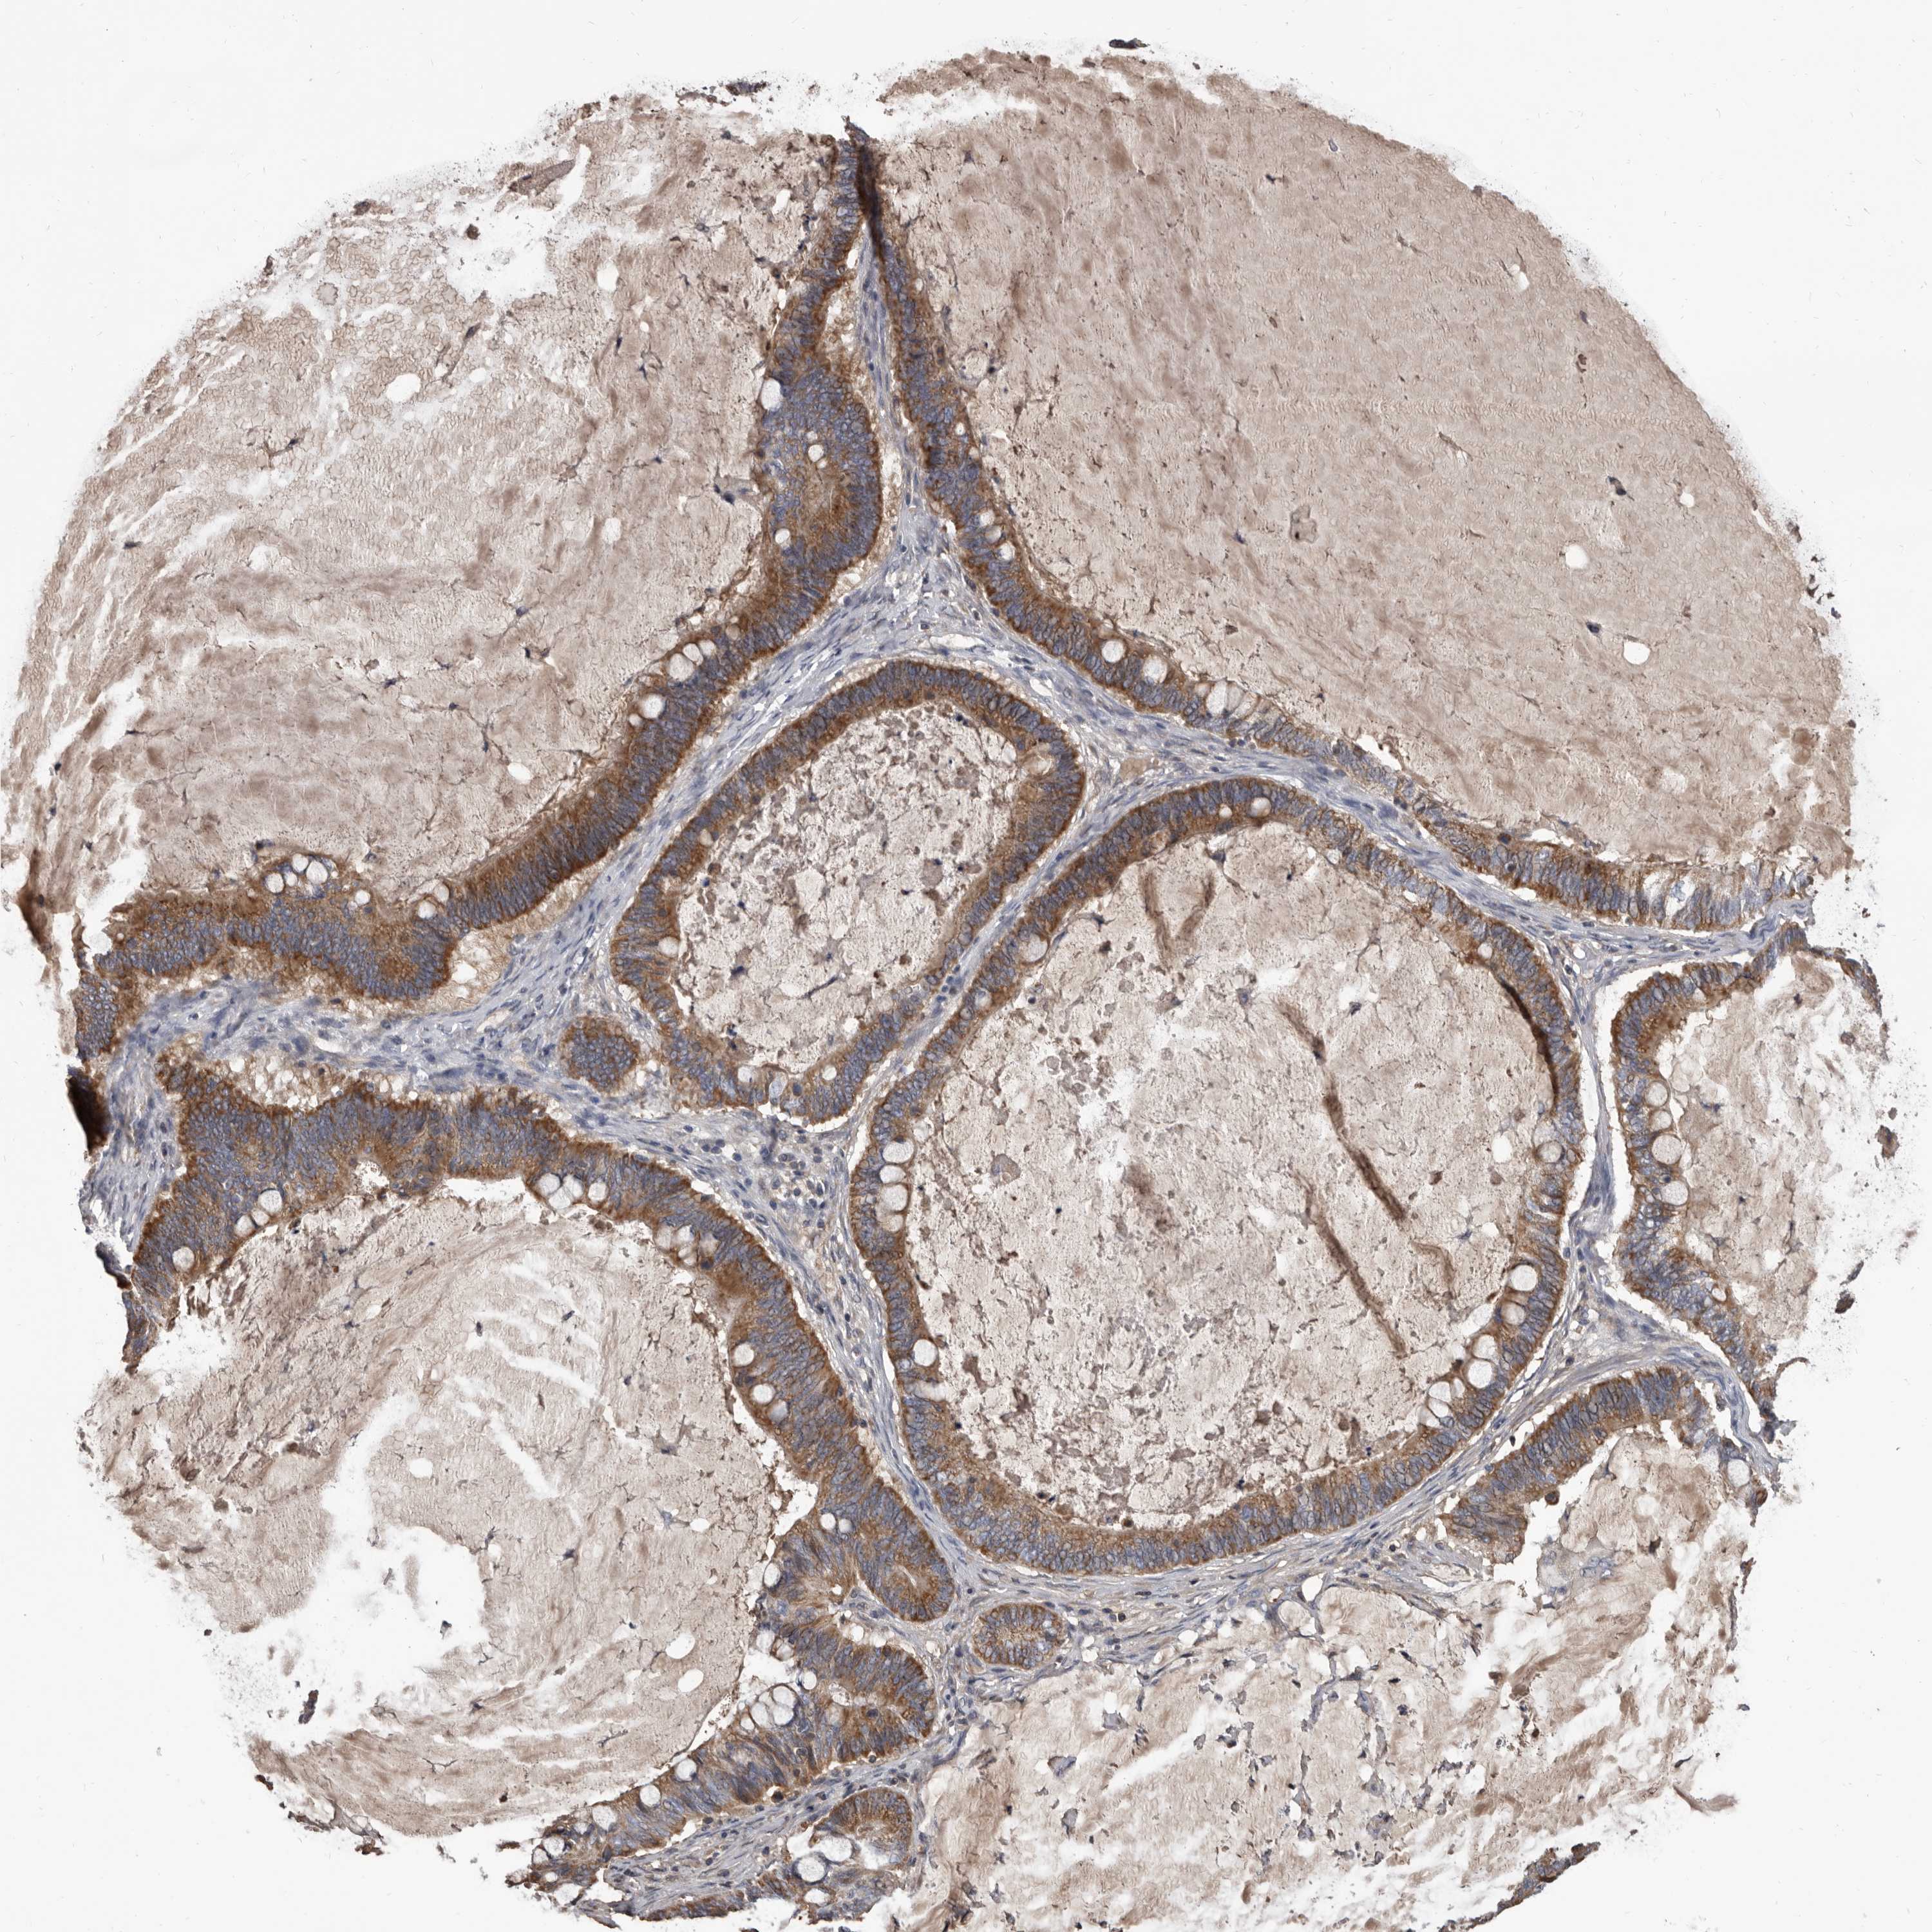

OVARIAN CANCER - Protein expressioni

A mouse-over function shows sample information and annotation data. Click on an image to view it in a full screen mode. Samples can be filtered based on level of antibody staining by selecting one or several of the following categories: high, medium, low and not detected. The assay and annotation is described here.

Note that samples used for immunohistochemistry by the Human Protein Atlas do not correspond to samples in the TCGA dataset.

Antibody stainingi

Antibody staining in the annotated cell types in the current human tissue is reported as not detected, low, medium, or high, based on conventional immunohistochemistry profiling in selected tissues. This score is based on the combination of the staining intensity and fraction of stained cells.

Each image is clickable and will lead to virtual microscopy that enables deeper exploration of all samples and also displays staining intensity scores, fraction scores and subcellular localization as well as patient and tissue information for each sample.

Antibody HPA029715

Antibody HPA029716

Cystadenocarcinoma, serous, NOS

Carcinoma, endometroid

Cystadenocarcinoma, mucinous, NOS

Carcinoma, NOS